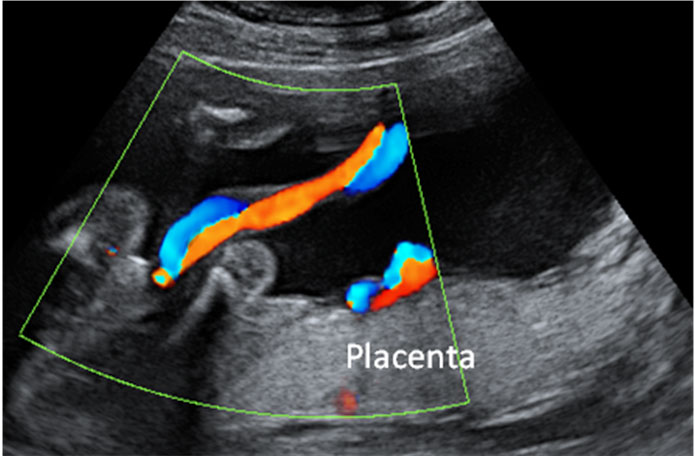

Cómo es un cordón umbilical visto con eco Doppler

En una ecografía Doppler en color, la sangre se colorea en rojo o en azul, dependiendo si se acerca o se aleja de la sonda del ecógrafo. En esta imagen vemos el cordón umbilical de un bebé (en dos colores) y la placenta.

Cordón umbilical visto con ecografía Doppler color